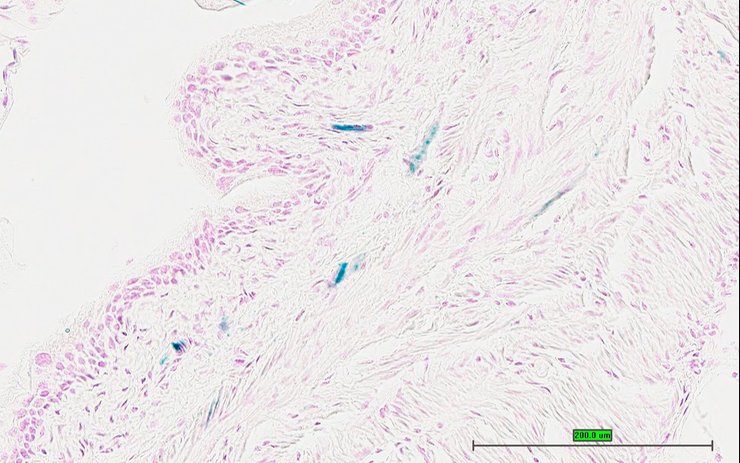

Specimen UC Davis_1879031: postnatal adult; Pmchtm1.1(KOMP)Vlcg/Pmch+ (more )

Structure Level Pattern Image Note

TS28: stomach Present UC Davis_1879031